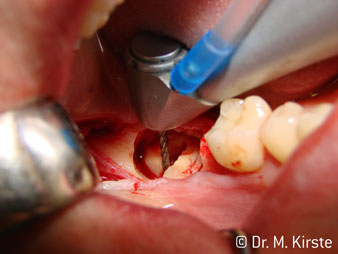

Die Winkelwahl des 45° Handstücks bringt viele Vorteile in der Anwendung. Chirurgisch tätige Kollegen, und für diese ist das Handstück in erster Linie entwickelt worden, werden schnell bemerken, dass man sehr gezielt arbeiten kann. Insbesondere bei der Weisheitszahnentfernung (Abb. 2) bedarf es keiner großen Weichteilabspreizungen im Wangenbereich (Abb. 3). Die Handstückkopfgestaltung kombiniert mit leichten Kopfdrehungen bei der Präparation lassen ein sicheres und schnelles Arbeiten im retromolaren Bereich zu.

Die professionelle Lagergestaltung im Innenleben des Handstückkopfes garantiert einen ruhigen Lauf der Bohrer, bei der Zahn- oder Wurzelseparation (Abb. 4 - 9) zeigt sich ein beeindruckendes Schnittbild ohne Schlageffekte.